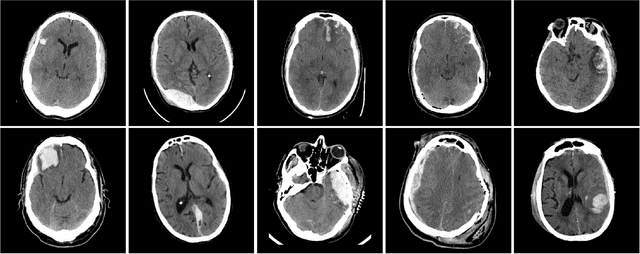

Abstract:Machine learning models are becoming commonplace in the domain of medical imaging, and with these methods comes an ever-increasing need for more data. However, to preserve patient anonymity it is frequently impractical or prohibited to transfer protected health information (PHI) between institutions. Additionally, due to the nature of some studies, there may not be a large public dataset available on which to train models. To address this conundrum, we analyze the efficacy of transferring the model itself in lieu of data between different sites. By doing so we accomplish two goals: 1) the model gains access to training on a larger dataset that it could not normally obtain and 2) the model better generalizes, having trained on data from separate locations. In this paper, we implement multi-site learning with disparate datasets from the National Institutes of Health (NIH) and Vanderbilt University Medical Center (VUMC) without compromising PHI. Three neural networks are trained to convergence on a computed tomography (CT) brain hematoma segmentation task: one only with NIH data,one only with VUMC data, and one multi-site model alternating between NIH and VUMC data. Resultant lesion masks with the multi-site model attain an average Dice similarity coefficient of 0.64 and the automatically segmented hematoma volumes correlate to those done manually with a Pearson correlation coefficient of 0.87,corresponding to an 8% and 5% improvement, respectively, over the single-site model counterparts.